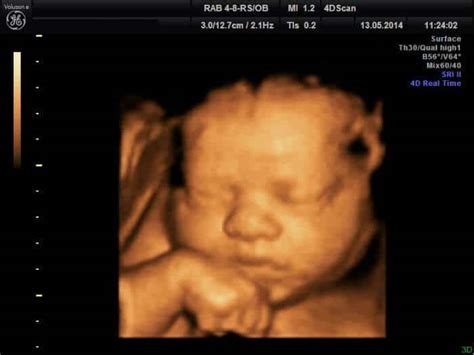

Niektorí muži však môžu mať z ultrazvuku zmiešané pocity. Napríklad 4D ultrazvuk v 19. týždni môže spôsobiť nepríjemný pocit, ak bábatko ešte nemá vyvinutú tváričku a zobrazenie je skôr čiernobiele alebo žlté. V takomto prípade je lepšie vidieť dieťatko, keď je už viac vyvinuté, alebo ak je zobrazenie čiernobiele, kde je lepšie viditeľná hlavička, nohy a celková stavba tela.